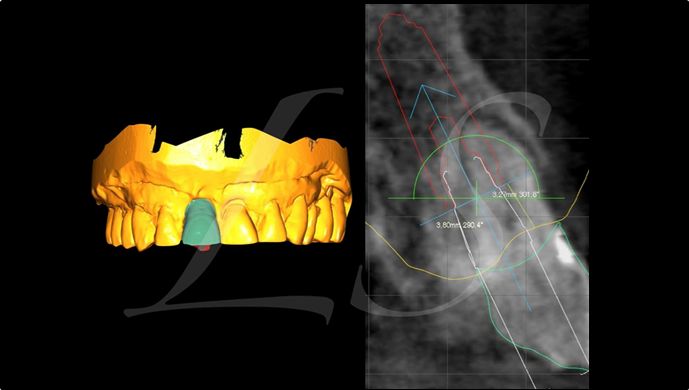

“ One implant /One tooth/ One hour step-by-step

+ associated connective graft ”

Clinical case: EImmediate implant placement & loading of #35 extraction socket with defect

- Courtesy of Dr. Kwang Bum Park, Korea -

Dr. Laurent Sers, immediate loading, digital guided surgery, digital ONE-DAY implant, maxillary anterior, #21, guided surgery, immediate loading, AnyRidge, R2GATE, Mega ISQ, R2GATE Full Surgical Kit

implant system, R2GATE Guide, R2GATE surgical kit (AnyRidge), Mega ISQ

“Automated customized drilling protocols for optimum implant stability/ ONE-DAY implants ”